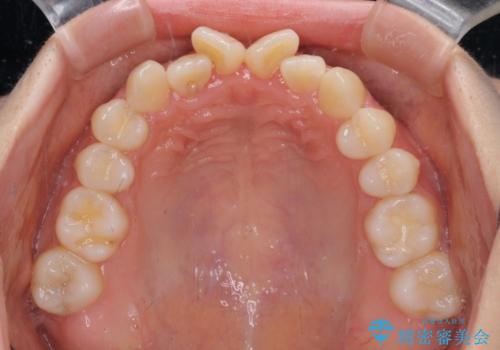

- 前歯のデコボコと非接触の上下前歯を気にして来院された患者様です。

上下前歯の隙間は舌の突出癖によるもので、隙間改善のためには舌のトレーニングがとても重要となります。

口元の突出感はないため、抜歯矯正の適用ではありませんが、デコボコを解消する際に外側に拡大されてしまうと治療前と比べて出っ歯になった印象にもなるため、舌の突出癖の改善が必須となります。

舌のトレーニングは、突出癖がなくなるまで必要であり、矯正治療後に突出癖が残ると、あっという間に隙間が空き、後戻りでデコボコとなってしまいます。